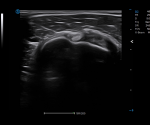

Click on images to enlarge

Click on images to enlarge

Full Volume Imaging and Coronal Section with High Clinical Value

IBUS acquires volume data from multiple sections to provide abundant information. The coronal section intuitively shows the anatomical information of breast tissue in a supine position during operation, which helps surgeon to perform more accurate surgical planning.